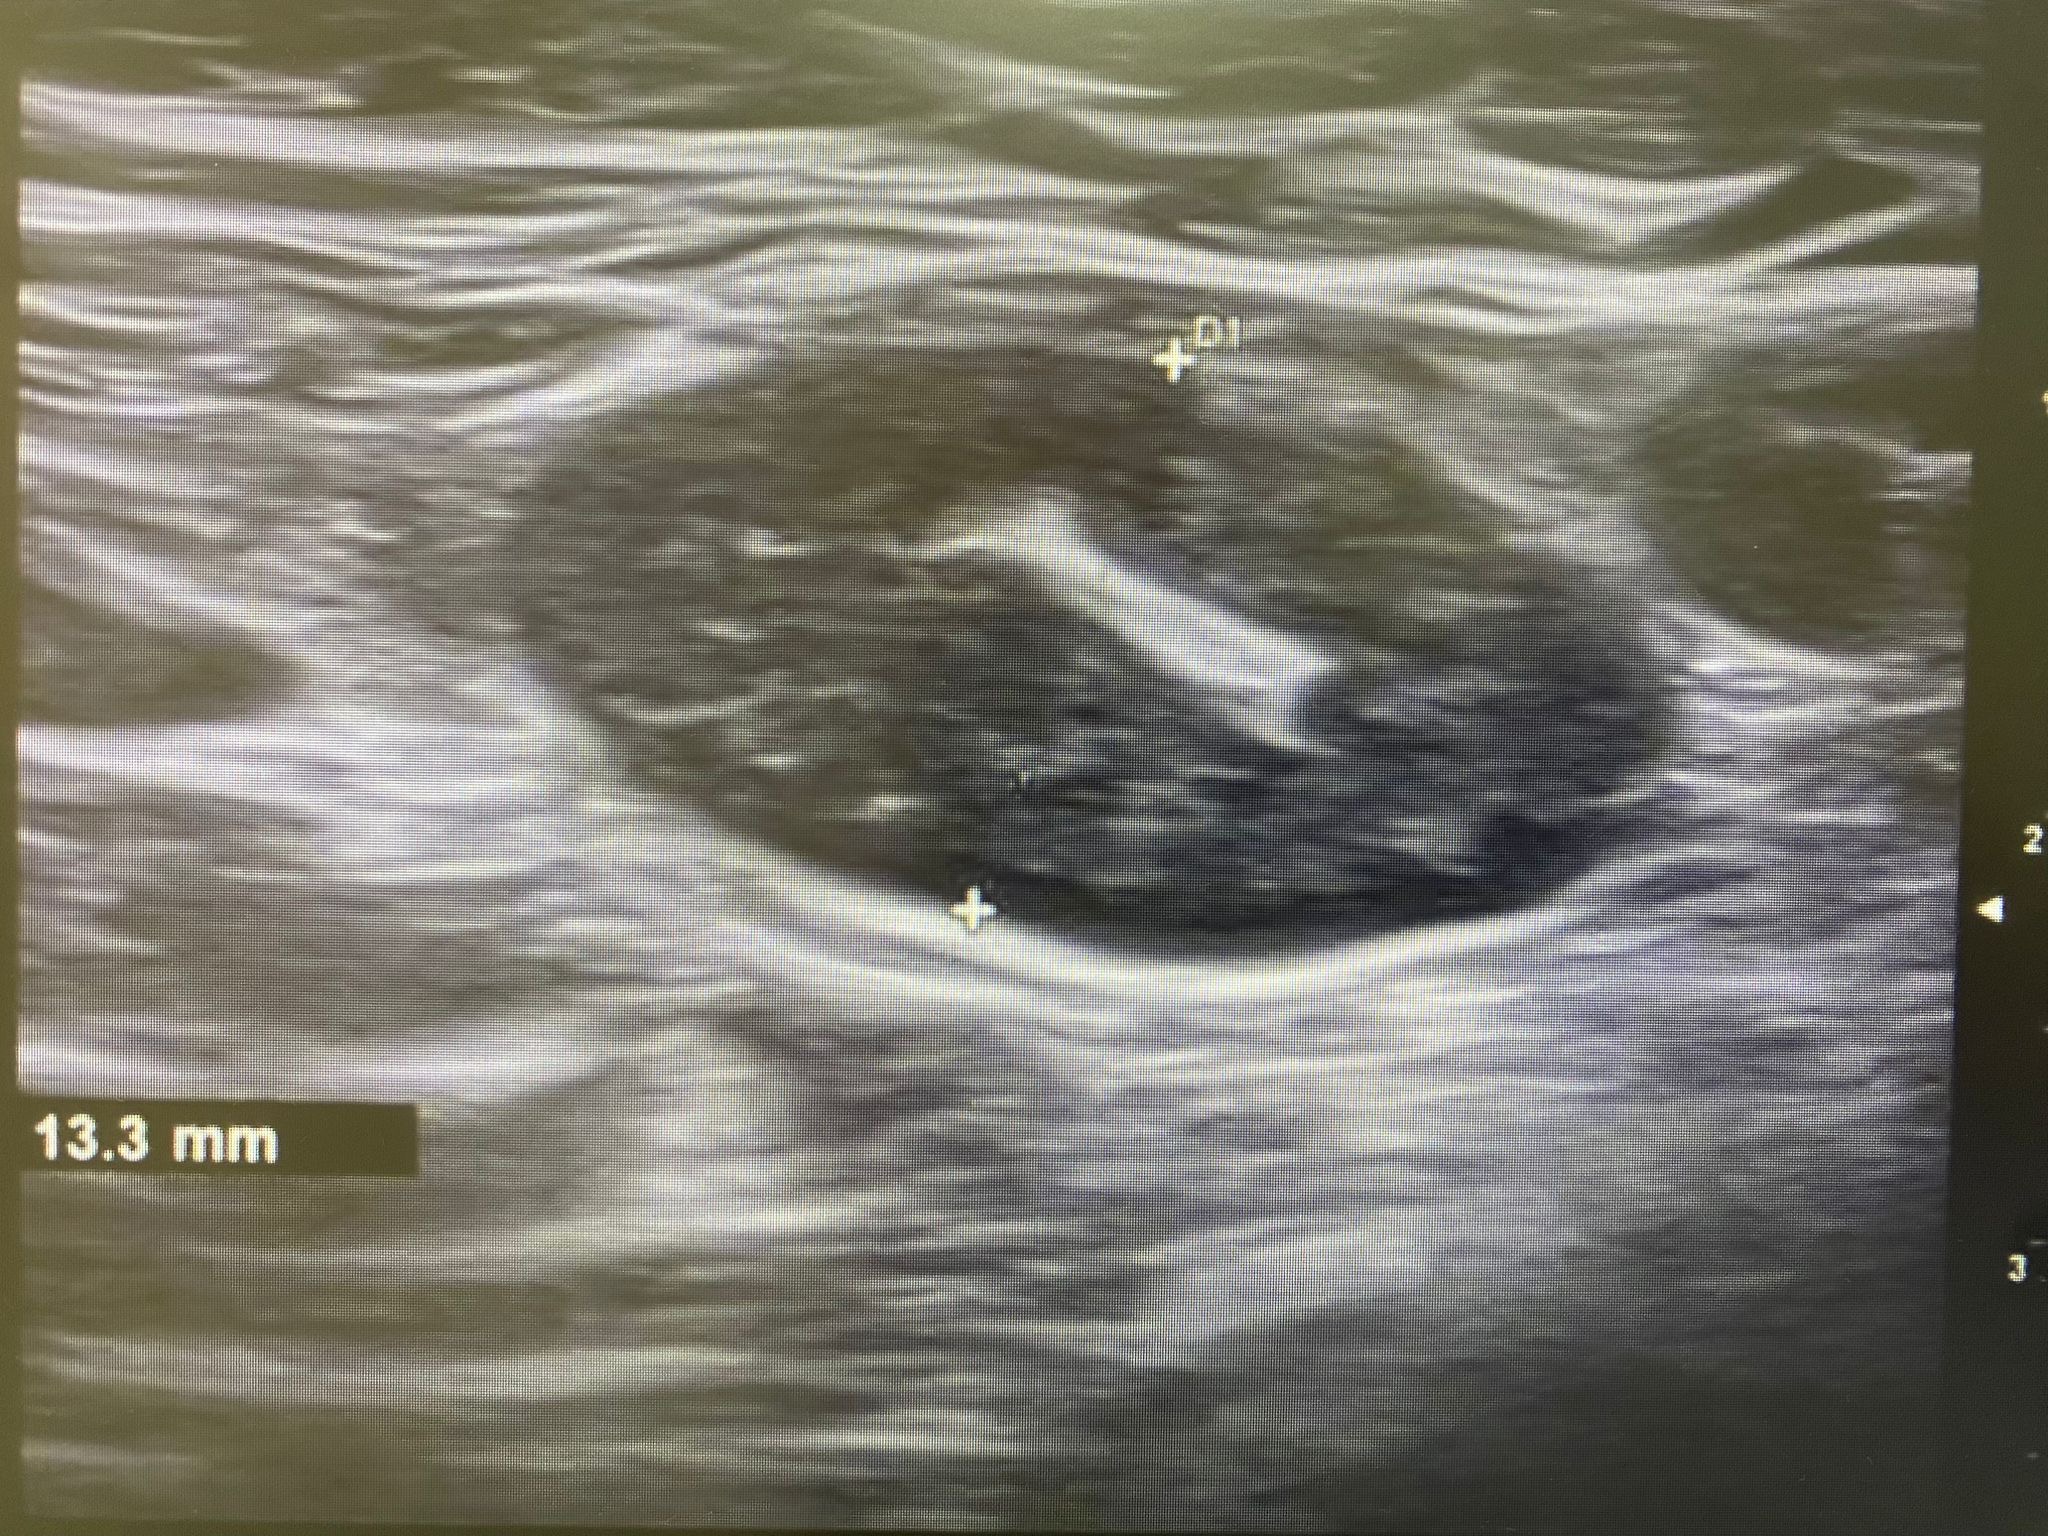

Ecografía: Valoración de adenopatías para acercamiento diagnóstico (típicas/atípicas).

Adenopatías patológicas, algunas redondeadas, con eje anteroposterior > 1 cm, parénquima homogéneo, cortical engrosada aunque con hilio respetado.

Ecografía axilar: múltiples adenopatías con eje corto > 2 cm y cortical engrosada.